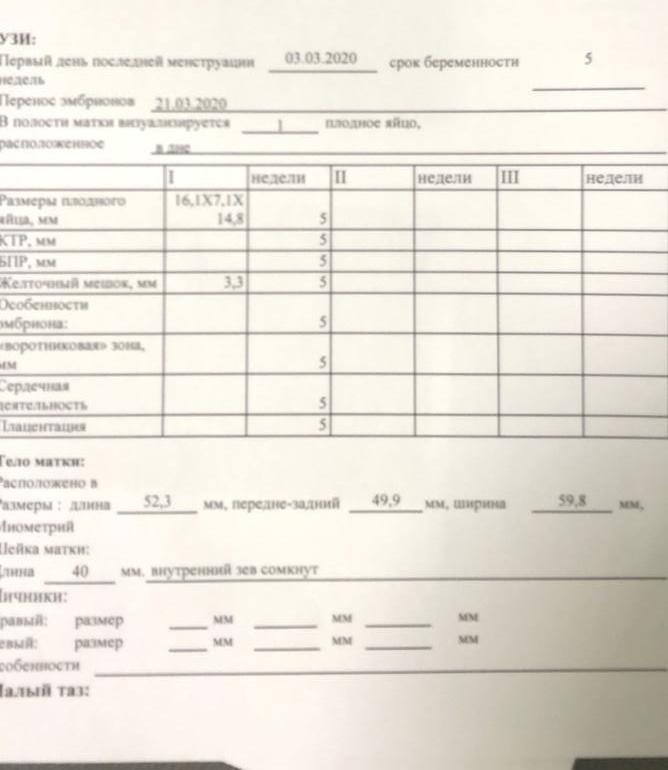

На узи ходила на21дпп